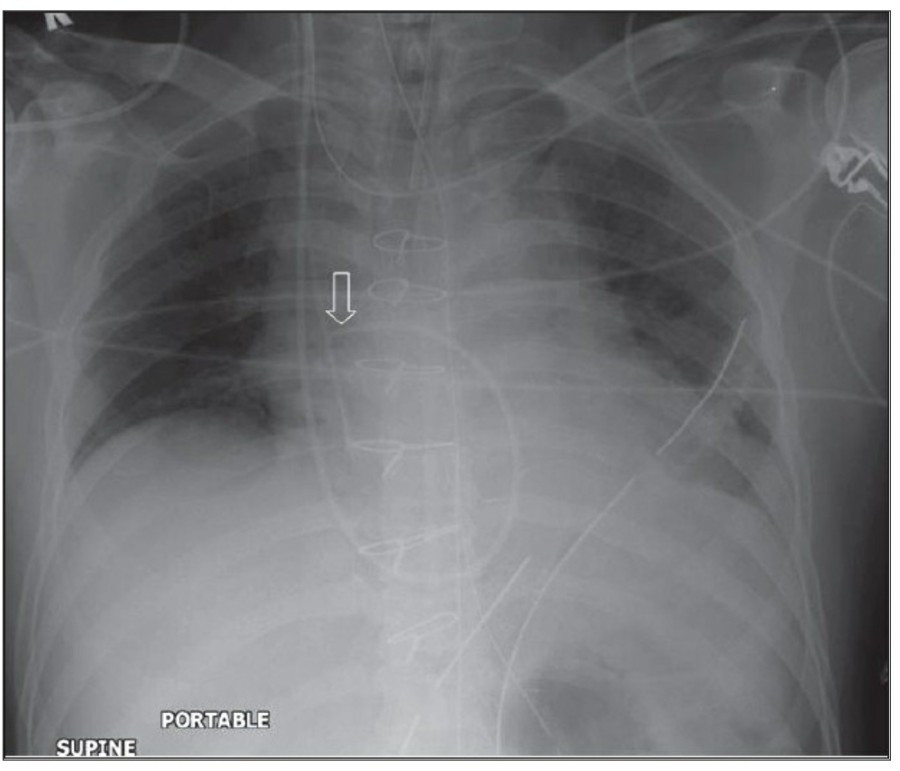

Pneumomediastinum

Pneumomediastinum은 mediastinum 안에 공기가 있는 경우를 일컬으며, intubation된 환자에서 구심적으로(centripetally) pulmonary interstitial dissection이 일어나는 경우와 관련이 있다.

또한 Mediastitnal air는 major airway 손상으로 인한 leakage나 retroperitoneum으로부터 fascial plane을 따른 air dissection에 의해 발생하기도 한다. Pneumomediastinum은 목까지 공기가 진행이 가능하고, pneumopericardium은 이와는 다르게 심장의 밑 부분으로 진행한다. Pneumomediastium은 일반적으로 무증상이지만, 간혹 청진 시 restrosternal crunch가 들릴 수 있다. Chest X ray상에서 공기가 major vessel 주변이나 SVC의 medial border, azygos vein에서 surrounding lucency로 보일 수 있다. 또한 aortic knuckle, descending aorta, pulmonary artery의 윤곽으로 나타날 수도 있다. Posteromedial pneumomediastinum은 주로 esophageal rupture의 결과로 나타날 수 있는데, praspinal costophrenic angle과 left diaphragm의 praietal pleural로 air dissection이 가능하다. 이 결과 V-sign of Naclerio라고 불리는 V-shaped lucency가 발생한다.

Pneumopericardium

Myocardium과 pericardium 사이에 공기가 존재하는 pneumopericardium은 pneumothorax의 합병증으로 발생 가능하지만 대부분은 심장 수술 후에 발견된다. Chest X ray 상에서 heart 주변으로 main pulmonary artery까지 진행된 lucent line으로 관찰된다. 공기는 cardiac shadow 아래에 모이는데 이는 continuous diaphragm sign으로 불리는, diaphragm 위의 midline을 건너는 소견이 나타난다.